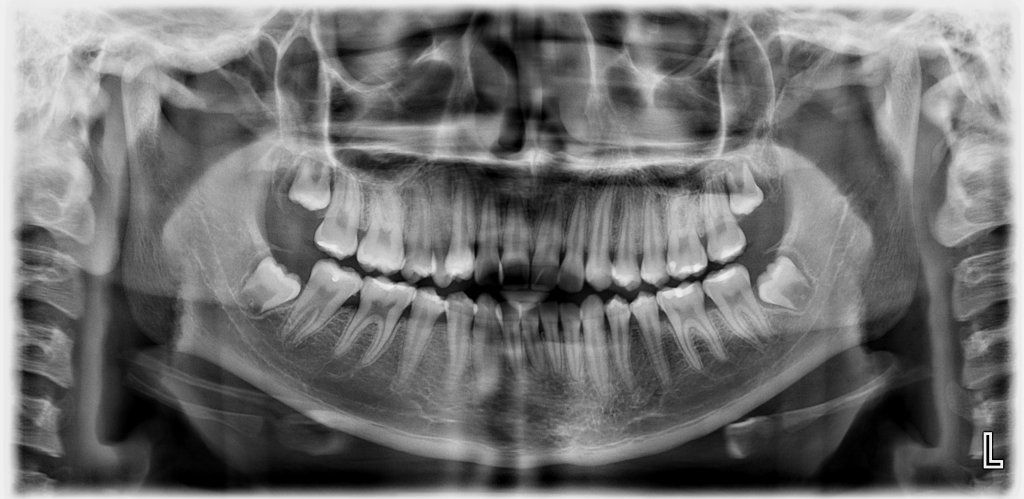

- Ortopantomografía

- Placas panorámicas dentales

- Radiografía panorámica dental